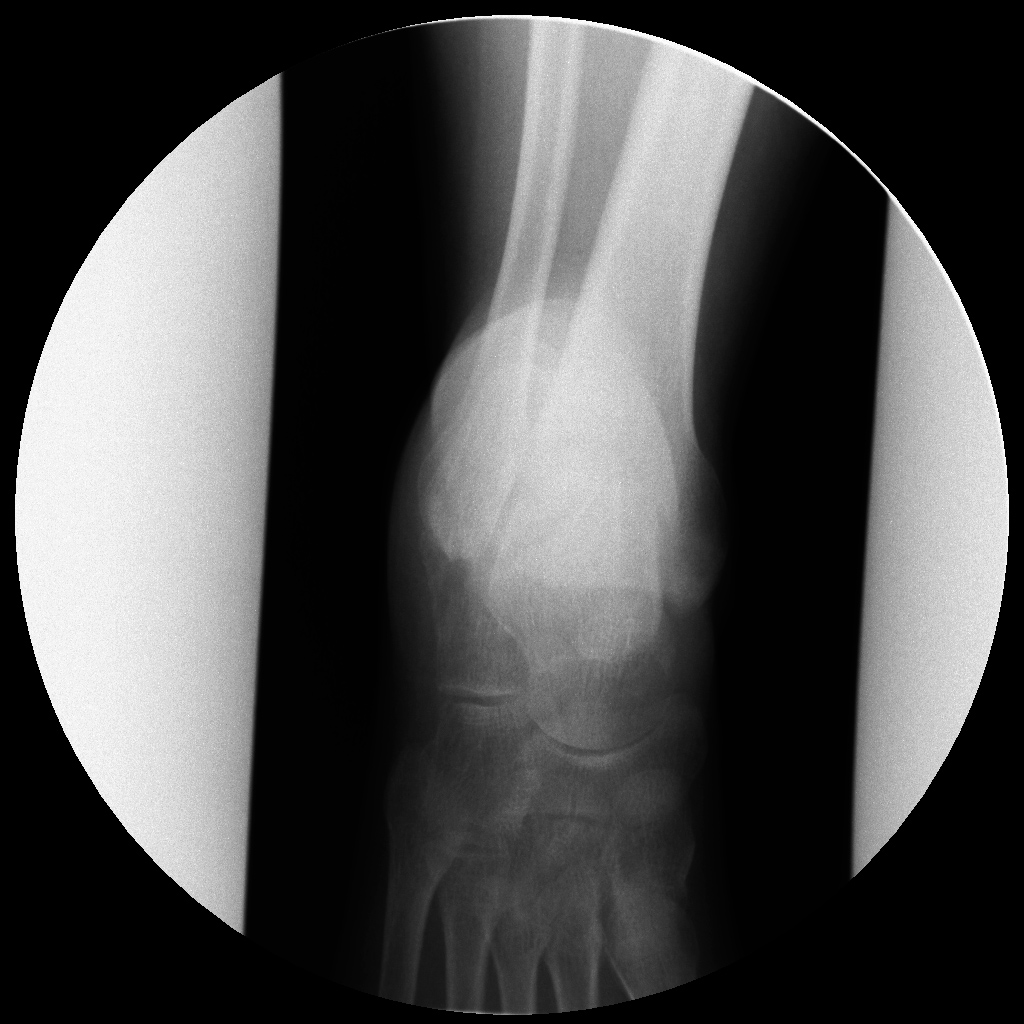

Женщина, возраст 55 лет.,вес 60кг.11.11.13 Падение с высоты 3х метров на ногу. сильная гематома на внутренней и внешней поверхности стопы. При первичном осмотре в республиканской больнице (г.Сухум) установлен диагноз: ушиб. Пациент отпущен домой.28.11.13 Сильные боли в течение двух недель.Сделан повторный рентген. Гематома спала, но полностью не рассосалась, боли уменьшились. Вторичный осмотр в военном госпитале (г.Агудзера).Диагноз: Осколочный перелом пятки со смещением.Лечение: Наложен гипс.Снимки прилагаю. Прошу помощь, по возможности, определить точность диагноза и лечения. Спасибо.

Снимок №2

Кликните для загрузки файла 2.jpg

Перелом пятки. Если есть возможность сделать малоинвазивный остоетсоинтез - то сделать, если нет - можно и консервативное, результат должен быть удовлетворительный.